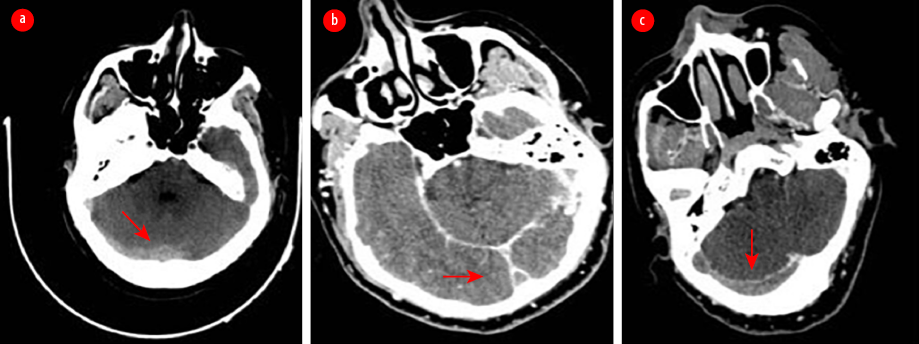

All blood tests, including the basic tests and those for vasculitis and thrombophilia, and spiral computed tomography (CT) of the chest, came back normal. A CT scan of the brain with and without contrast and CT cerebral venography revealed a picture consistent with extensive cerebral venous thrombosis (CVT) [Figure 2].

Figure 2: (a) Non-enhanced axial CT of the brain revealed hyperdense transverse sinuses on the right side as well as edema in the right occipitoparietal regions. (b) An enhanced axial CT of the brain showed an empty delta sign due to thrombosis in the superior sagittal sinus. The sign consists of a triangular area of enhancement with a low-attenuating center, which is the thrombosed sinus. (c) An axial CT venogram shows no flow in the right transverse and right sigmoid sinuses, with a filling defect due to thrombosis.